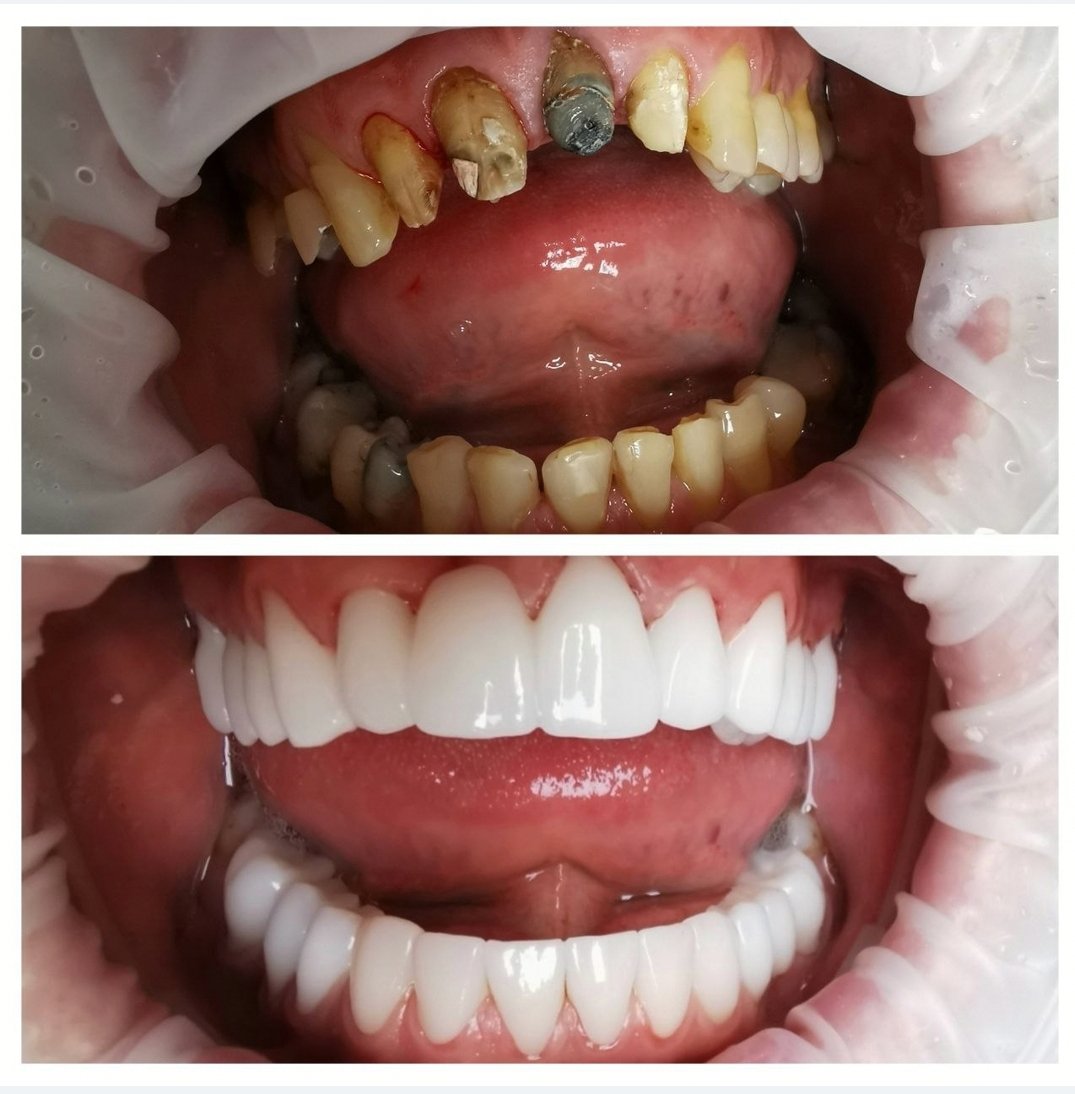

Fotografie